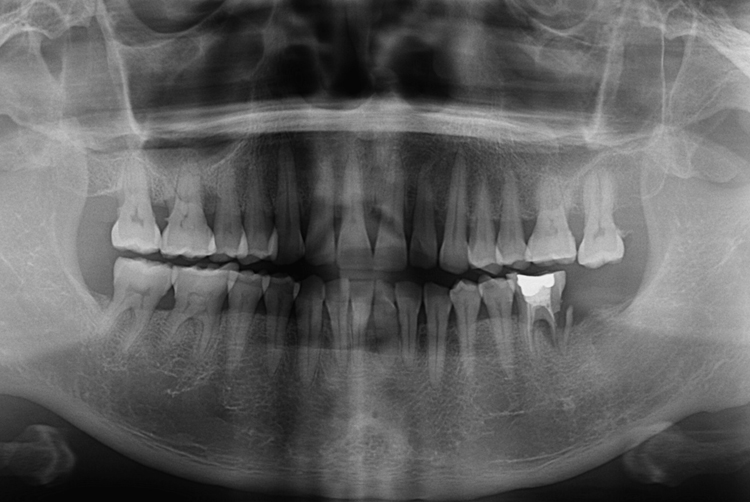

[임플란트] 어금니 임플란트

치료전 : 2018-07-19